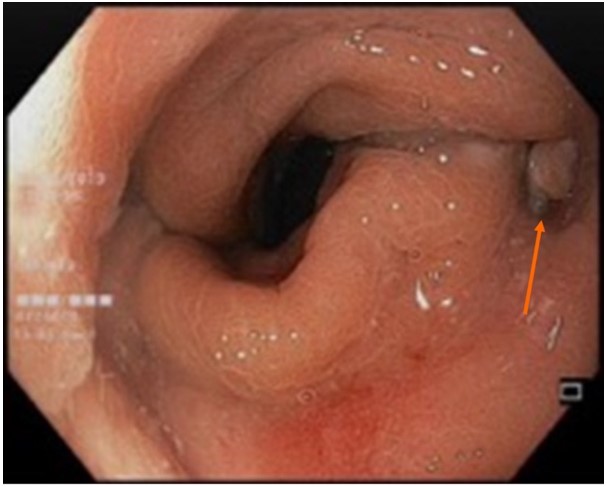

Figure 3: Endoscopic image of a small anastomotic sinus (pointed by the arrow).

Patients A, D, and E developed varying degrees of anastomotic complications at the previous colorectal anastomosis after ileostomy closure (Table 1), despite normal pre-operative results from pre-operative flexible sigmoidoscopy and contrast studies. These complications were primarily very small sinuses seen on endoscopy (Figure 3), without obvious pelvic collections on cross-sectional imaging. Nonetheless, these patients were primarily managed conservatively with flatus tube insertions, except for patient A, who required a diverting colostomy due to persistent colonic distension with subsequent development of a recto-prostatic fistula.